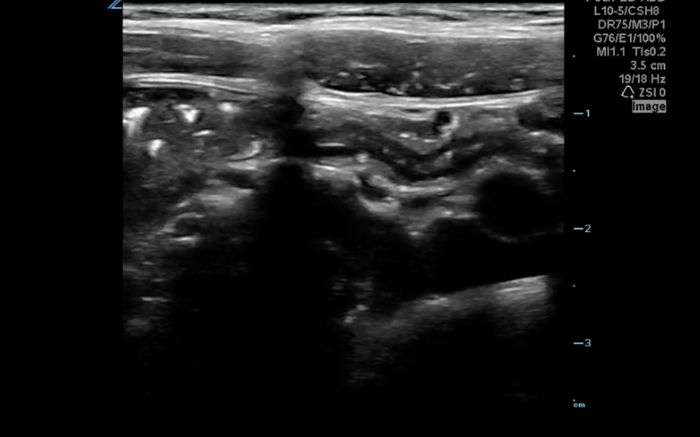

The linear probe is placed in the RLQ in the transverse position with indicator to the patient’s right. Identify the psoas muscle and iliac vessels lying medial. Once these structures are visualized, slide lateral and look superficially to identify the cecum. (Figures 1a,1b 1) Use graded compression-progressive increase and decrease of pressure to move any gas out of view. Keeping the lateral edge of the abdominal cavity in view (Figure 2), the ultrasound probe should slide cranial in traverse plane, visualizing the ascending colon until the hepatic flexure.  In this location, the colon turns just medial to the liver with the kidney deep in the view. (Figure 3) This is the most common location to identify ileocolic intussusception. If no tissue mass is identified, the probe should be turned to the sagittal plane with indicator toward the head (to keep the colon visualized in the transverse view) and moved across the transverse colon continuing to use graded compression to look for a tissue mass consistent with intussusception. Once at the splenic flexure (Figure 4), the probe should be transitioned back to the transverse orientation to interrogate the descending colon.

10-2024 Article7-2.jpgFigure 2. Lateral border of right abdomen maintained in view with “starry night” appearing stool in colon (white star), transverse abdominus muscles (triangle) and border of the peritoneal cavity (white arrow)